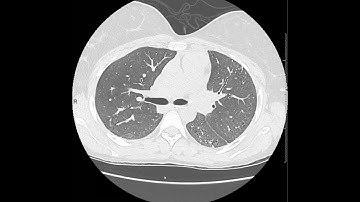

NSIP Explained